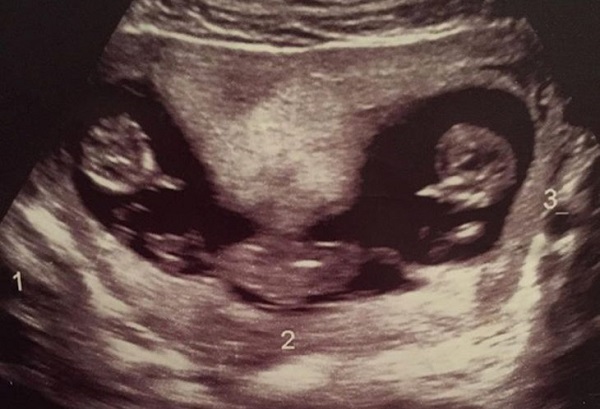

Cuando Allen llevaba nueve meses de embarazo, una situación severa la llevó al médico. La oriunda de Gateacre, Liverpool contaba con severos dolores de cabeza y una náusea increíblemente poderosa, causas suficientes para ser atendida.

Al llegar al nosocomio, le dieron la noticia de que serían trillizos tras una prueba. "No lo podía creer. Ni siquiera había pensado que podían ser mellizos, y eran trillizos. Y además, nunca habíamos tenido de estos en la familia" manifestó.

Los tres bebés Roman, Rocco y Rohan nacieron por operación cesárea pero mucho antes de que estuvieran durante cuidados intensivos por ser neo-natos durante seis semanas, el doctor a cargo de Allen quedó sorprendido al visualizar las pruebas de sangre realizadas.